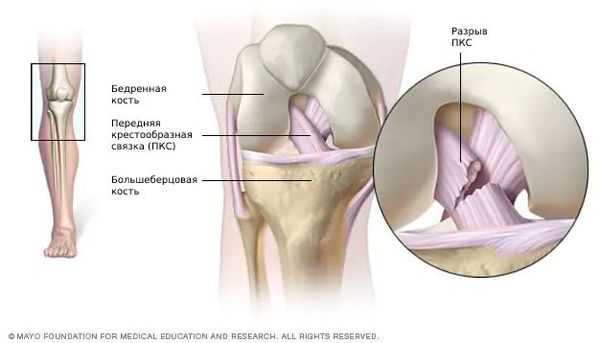

Разрыв передней крестообразной связки может произойти при действии силы, направленной вперед, на заднюю поверхность коленного сустава при согнутой и повернутой внутрь голени. Разрывы крестообразных связок могут сопровождаться отрывными переломами костных пластинок в местах прикрепления связок или переломом межмыщелкового возвышения. Что значительно затрудняет последующее лечение. Очень часто разрывы крестообразных связок происходят у спортсменов во время игры в футбол, при занятиях горнолыжным спортом, у борцов. Задняя крестообразная связка разрывается при резком разгибании голени в коленном суставе или при прямом ударе по передней поверхности голени, когда она согнута в коленном суставе.

Передняя крестообразная связка отвечает за динамическую устойчивость коленного сустава, фиксируя голень от нефизиологического смещения кпереди и поддерживая наружный мыщелок большой берцовой кости. Более 1/2 стабильности коленного отдела обеспечивается благодаря ПКС. Именно поэтому данную структуру специалисты называют первым стабилизатором колена, без нее сустав нормально работать не сможет. Располагается она в самом центре костного соединения, перекрещиваясь с задней крестообразной связкой х-образно, что и дало этим двум структурным элементам одноименные названия. Мы же будем говорить сейчас конкретно о ПКС и посттравматической реконструктивно-пластической ее коррекции.

Внимание! Полностью разорванная передняя крестообразная связка коленного сустава без пластики не способна самостоятельно соединиться и срастись. Поэтому для возобновления ее функциональности, если дефект действительно серьезен, назначается артроскопическая процедура с целью восстановления целостности ПКС.